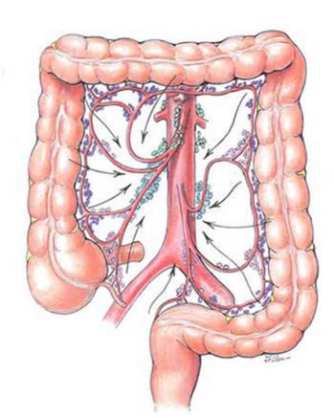

Crohn xəstəliyinin yayılma xüsusiyyəti necədir?

Nazik bağırsaq, kolon və ya hər ikisi zədələnə bilir, “sağlam aralar” yəni zədələnmiş bölgələr arasında sağlam bağırsaq toxuması olur, ona görə də regianal enterit də deyilir.

Xoralı kolitin yayılma xüsusiyyəti necədir?

Daha çox rektum zədələnir, proksimala doğru yayılır, “sağlam aralar” olmur.

Crohn xəstəliyində intraoperativ nələr tapılır?

Nazik bağırsaqlarda divar qalınlaşması, “piy manjeti” (müsariqənin enterin antimezenterik divara doğru, irəliləməsi), qalınlaşmış və qısalmış mezenterium, fistul, abses